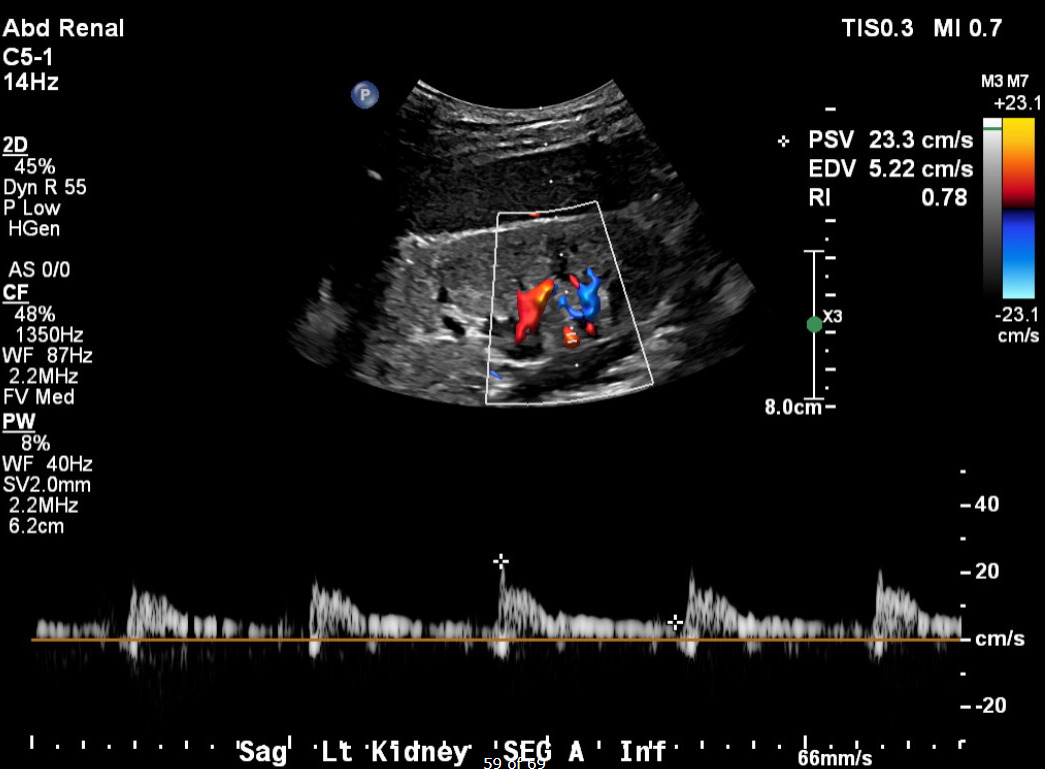

Her current presentation was characterized by a one-week history of worsening dyspnea, orthopnea, and paroxysmal nocturnal dyspnea. On arrival, her blood pressure was 257/169 mmHg, with tachypnea and bilateral inspiratory crackles on examination. Initial laboratory studies (Table 1) demonstrated serum creatinine 5.36 mg/dL, BUN 74 mg/dL, hemoglobin 8.2 g/dL, NT-proBNP >35,000 pg/mL, and high-sensitivity troponin T 93 ng/L, consistent with demand ischemia in the setting of hypertensive emergency. Urinalysis revealed 3+ proteinuria. Chest radiography demonstrated bilateral interstitial and alveolar opacities consistent with pulmonary vascular congestion. A transthoracic echocardiogram obtained during this admission demonstrated preserved LVEF (56–60%), severe concentric left ventricular hypertrophy, and grade I diastolic dysfunction. Renal duplex ultrasonography demonstrated bilaterally echogenic kidneys consistent with medical renal disease. Doppler interrogation of a segmental branch supplying the upper pole of the left kidney demonstrated elevated peak systolic velocity (~90.6 cm/s), absent end-diastolic flow (end-diastolic velocity 0.0 cm/s), and a markedly elevated resistive index (RI = 1.0) (Figure 1), findings which may suggest severe intrarenal hemodynamic compromise and a probable functionally significant focal upper-pole segmental renal artery stenosis. Flow velocities in the main renal arteries and other segmental branches were within normal limits (Figure 2). Computed tomographic angiography was not performed due to advanced renal dysfunction. Magnetic resonance angiography was also considered; however, it was not pursued during this hospitalization because additional imaging was unlikely to alter immediate management, particularly in the setting of advanced chronic kidney disease and the patient’s preference to avoid renal replacement therapy.

Several reports have demonstrated that unilateral renal artery stenosis may precipitate flash pulmonary edema when renal functional reserve is reduced, including cases involving contralateral kidney atrophy or solitary kidneys.4–6 These observations support the concept that loss of effective renal mass, rather than anatomic bilaterality alone, may reproduce the physiologic consequences traditionally attributed to bilateral disease. In our patient, advanced chronic kidney disease likely amplified the hemodynamic impact of the focal segmental lesion, allowing a localized vascular abnormality to produce recurrent systemic decompensation. Building on this, the case further emphasizes the importance of thorough renovascular evaluation, even when abnormalities appear subtle. Segmental or branch-level renal artery stenosis can be missed when diagnostic evaluation is limited to the main renal arteries, as Doppler criteria validated for main artery disease may not reliably identify focal branch involvement⁷. Seoung et al. showed that systematically comparing intrarenal Doppler waveforms across multiple renal segments (upper, mid, and lower poles), and noting significant regional hemodynamic differences, can suggest the presence of a hemodynamically important focal lesion.7 In this case, duplex ultrasonography demonstrated abnormal renal arterial hemodynamics confined to an upper-pole segmental branch (Figure 1), while waveforms in other intrarenal segments were preserved (Figure 2). This regional disparity may support the presence of focal segmental renovascular disease. This pattern has been reported as a cause of renovascular hypertension but remains susceptible to under recognition.7